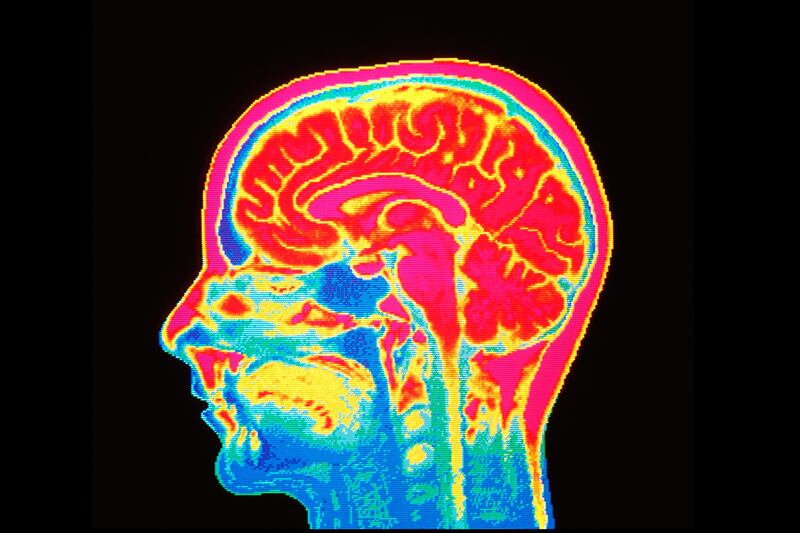

The study analyzed the MRI scans of 56 male participants, a group that included 13 homosexual pedophiles and 11 heterosexual pedophiles, exposing them to “high arousing” images of men, women, boys, and girls. Participants then ranked each photo for attractiveness, leading researchers to their conclusion that the brain network of pedophiles is activated by sexual immaturity.